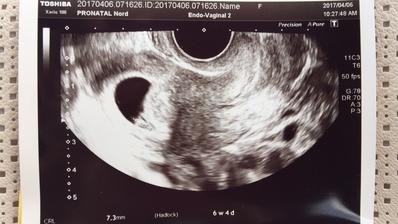

@dagmarka13 ahojky zitra me ceka prvni uktrazvuk. Ted jsem delala jeste jeden kontrolni test jestli neslabne a ok. Zaludek zlobi, bricho obcas da o sobe vedet tak beru na doporuceni dr magnesium a taky lehke spineni, ale to by melo byt v tom 6tt v poradku. To vis strach mam, ale uz se chci radovat ❤️🤰🏻